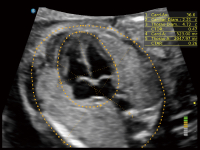

作为开立医疗全新打造的超高端旗舰超声产品,从探头抬起唤醒开启扫查到多维探头发射接收,通过先进的场成像发射、自适应聚合重建等技术,基于RF Data原始射频数据在图像生成、高端功能等方面实现突破,为妇产科、儿科提供全方位临床解决方案。

梦溪®P80以“关爱女性”为基石,提供全方位的解决方案,量身定制以满足女性的健康需求,涵盖妇科、生殖健康检查、产前筛查及产后康复等领域。